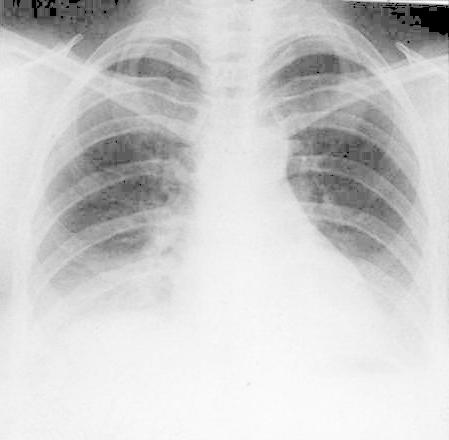

POSITION

of the SCAPULAE

They should project outside the lung fields

wrong--->

correct: